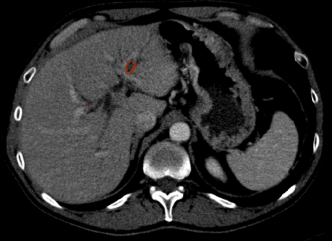

After having the liver segmented, we might directly apply a 3D segmentation network to extract the liver lesions. However, a 3D Network operating only in the liver region is still computationally expensive and may suffer from the problem of lacking 3D training scans. In order to mitigate these issues, we propose to use a mixed network to handle the segmentation of large and small lesions separately. In particular, we use a 2D network to scan slice-by-slice and predict larger tumors if present. However, this method is not sufficient for predicting small lesions, as the false positive examples shown in Fig. 3. This happens due to the appearance of the small lesion matching that of other tissues or vessels on 2D liver slices. A 3D network learning from cropped volumes with small lesions can reduce such false positives, because it leverages the observation that the location of the tissue or vessel appears to travel considerably in-between slices whereas the liver lesion constantly appears to be roughly stationary across slices. Regarding the threshold of the lesion size used to separate the large and small lesions, it may vary for different applications and datasets. Here, we set the threshold as a resolution of by experimentally testing on the LiTS dataset, which greatly balances the prediction accuracy and the computational efficiency.